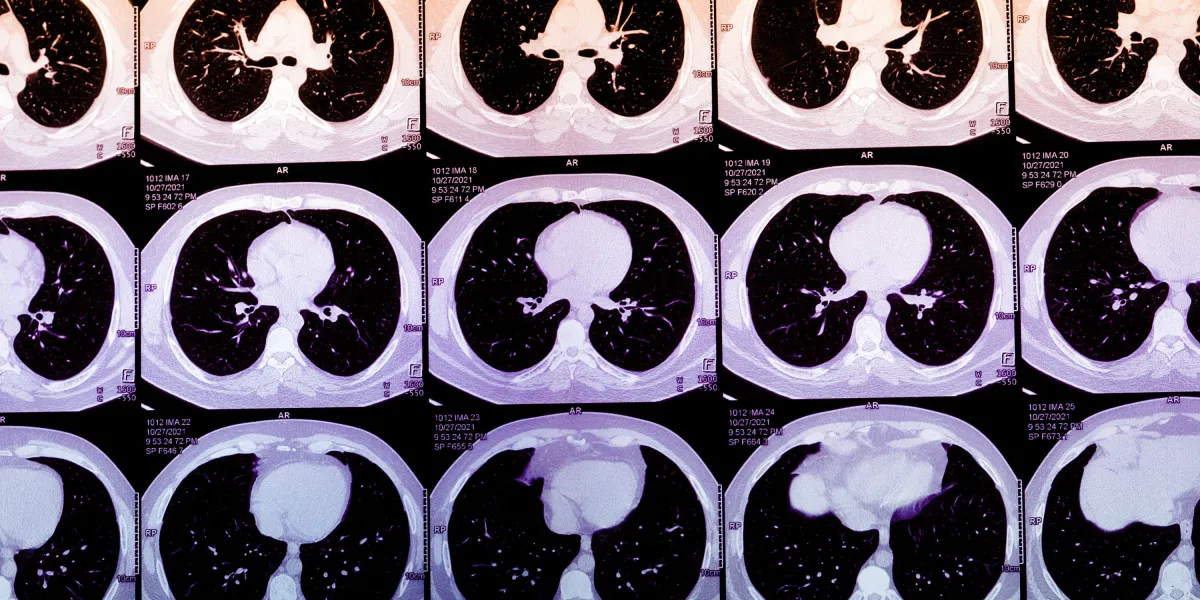

Dedicated testing for CAC remains an underutilized method of predicting heart attack risk. Over decades, plaque in heart arteries moves through its own life cycle, hardening from lipid-rich residue into calcium. Heart attacks themselves typically occur when younger, lipid-rich plaque unpredictably ruptures, kicking off a clotting cascade of inflammation that ultimately blocks the heart’s blood supply. Calcified plaque is generally stable, but finding CAC suggests that younger, more rupture-prone…